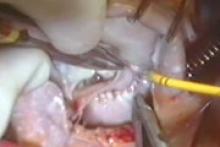

Cardiac surgeons largely have converted to reparative procedures for tricuspid valve disease. Recent STS database studies now show that 95% of tricuspid valve operations concomitant to mitral surgery involve repair. Most tricuspid disease etiologies such as secondary functional, primary organic, endocarditis, and congenital currently have good autologous solutions with low late failure rates.

Techniques that have been successful for mitral repair, such as full ring annuloplasty, artificial chordal replacement, and autologous pericardial leaflet augmentation, have facilitated the transition to repair. This video illustrates current repair methods in 8 patients with a variety of tricuspid valve disorders.